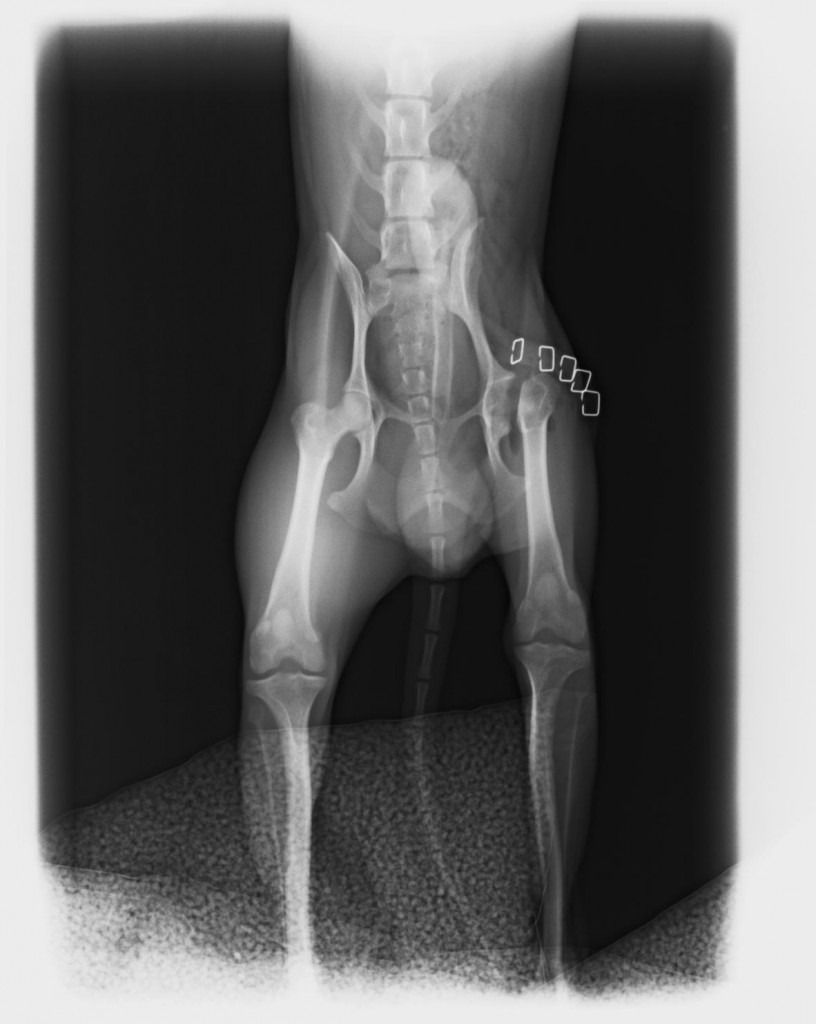

¿Necesitas radiografías oficiales de cadera?

Estamos acreditados para hacer las de cualquier raza

Displasia de cadera

Se trata de una enfermedad hereditaria, que se suele dar en razas como el pastor alemán, labrador, mastín, rottweiler, etc. Suele empezar a dar problemas a partir de los 7-8 meses de edad del cachorro, y es muy importante la detección precoz de la enfermedad.

El tratamiento puede ser

conservador, y si éste no funciona, pensar en un tratamiento quirúrgico. En este caso, cuanto antes hagamos la cirugía, mejor pronóstico va a tener nuestro perro.

Si lo que queremos es prevenir, es muy importante realizar radiografías si son de una raza predispuesta. Además, ofrecemos la posibilidad de realizar un Test Genético para labradores, mediante una muestra de sangre, y nos predice la capacidad de tener y transmitir la enfermedad a la descendencia.